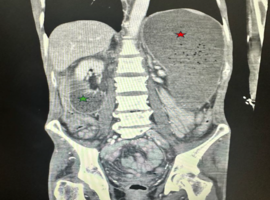

Identification of a PKD1 Non-truncating Variant Presenting with a Rapid Progression: A Case Report